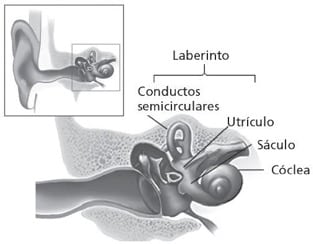

• Es una anomalía en el oído interno que afecta el equilibrio y la audición.